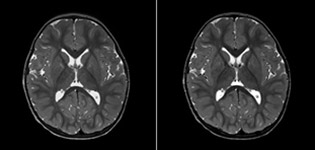

The value of susceptibility weighted imaging in visualizing brain injury is well documented. The Philips multi-echo SWIp technique provides fast susceptibility weighted imaging with enhanced susceptibility contrast and high resolution.

“Pediatric imaging is not without its challenges,” Dr. Miller says. “Since our patients are often very small, we need very high-resolution imaging. In cases of brain injury, we need to obtain information quickly so the treating clinicians can make decisions on care. We rely on high resolution and robust imaging capabilities, and SWIp provides that.”

“SWIp helps us identify blood or blood products, calcification, and diseases that affect the vascular system,” says Dr. Miller. “In children with traumatic brain injuries, it highlights areas that are injured, better than some of the previous techniques that we were using. These children often have micro-injuries that cause small amounts of blood or tissue damage. Adding SWIp helps us to better characterize the extent and nature of the injury. Having characterized an injury to the extent of what’s possible supports our diagnostic confidence.”

Full adoption after initial comparison

“I would definitely recommend other users to implement SWIp. We initially added the SWIp sequence following a lot of support for its utility in the literature. Then we directly compared SWIp to the 2D gradient echo sequences that we were using. After a good amount of clinical experience in seeing its benefits, we were confident to replace the old sequences with SWIp. It gives us a better assessment of the physiological processes of the brain that were less apparent on our previous imaging sequences,” says Dr. Miller. “SWIp is now a routine sequence for imaging traumatic brain injury patients at PCH, and it’s episodically added for patients who have intracranial vascular abnormalities.”

“I believe SWIp is rapidly becoming the standard in imaging traumatic brain injury, because of its high sensitivity to venous blood products. SWIp may even help attract patients; our neurosurgeons often ask to have the patients imaged on our scanners with highly sensitive techniques like SWIp. There’s also a growing application of SWI sequences in other vascular abnormalities because of the possibilities around physiological assessment of the brain than just a standard structural imaging.”